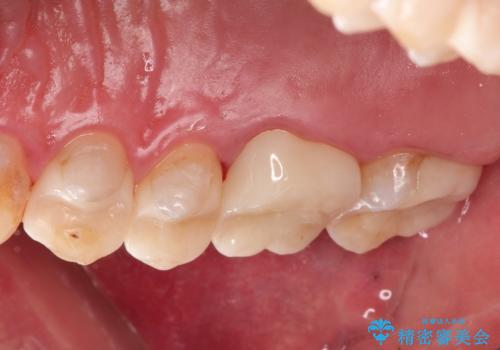

金属だらけの奥歯 根管治療のやり直しとセラミック化

→最終的にクラウンを製作し、きれいな奥歯を獲得する

かぶせ物の種類:Bellezza

詰め物の種類:e.max press In